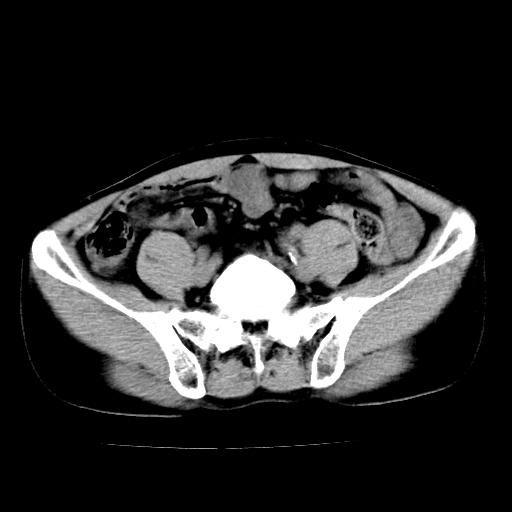

男,47岁,左输尿管结石碎石治疗后10余日。彩超示:左输尿管下段狭窄、输尿管积水。请各位讨论一下左输尿管下段结石还是静脉石?

象是第二狭窄处结石伴以上输尿管、肾盂轻度积水。

输尿管结石伴以上输尿管、肾盂轻度积水。

两侧髂总动脉壁斑状及点状钙化.左侧输尿管行经与左髂总动脉相交后见高密度影,且下段输尿管管腔未见扩张,应该要考虑结石伴以上输尿管及肾盂积水.但右侧结节状高密度影,也应该是结石吧!那以上输尿管未见扩张呢!因此静脉结石可能性也较大.请问楼主碎石前左侧输尿管结石位置.

虽左侧有轻度肾盂积水但不支持结石。1结石边周应该有软组织包绕呈晕征。2钙化点前面见输尿管影也不支持是结石。3彩超没提结石。建议超生复查。

输尿管先位于腹部,后进入盆腔,最后斜穿膀胱壁开口于膀胱,因此,临床上常将输尿管分为腹段、盆段和壁内段。第1个狭窄:在肾盂与输尿管移行处。第2个狭窄:在跨过髂血管处。第3个狭窄:在穿过膀胱壁处。这些狭窄是结石容易滞留的部位。

左侧输尿管有轻度扩张伴有肾盂积水,输尿管下段周围的高密度影不象在输尿管内。

同意,不支持结石。(因显示该高密度影前见扩张输尿管影,另外两侧对称显示)。

左侧高密度影在左侧输尿管的内侧方,所以不考虑输尿管结石.

我认为不是结石的可能性大,因为他的位置和血管钙化的位置邻近